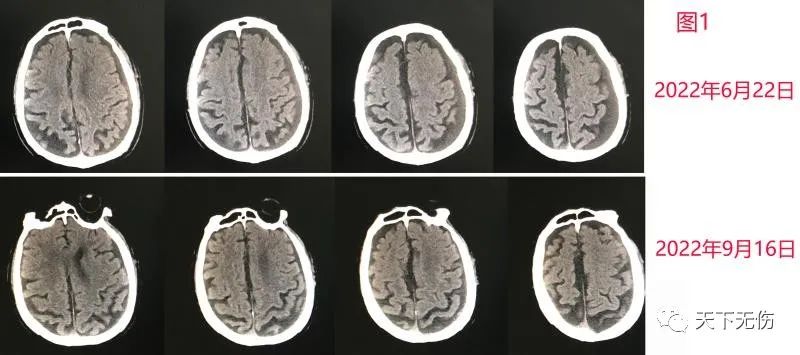

昨天老人因为其他疾病又请我会诊,也因此才复查了头CT,结果我和放射科主任一起诊断:血肿已经完全吸收(图1)。这为他汀单药治疗慢性硬膜下血肿有效添了新证据。

图1